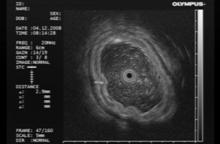

По данным ЭУЗИ, эндосонограммы пациентов со всеми формами лимфом демонстрируют их отличительный признак - в области визуально измененной слизистой оболочки при сканировании стенка желудка утолщена за счет гиперэхогенного неоднородного подслизистого и глубоких слоев слизистого слоя, а между патологическими зонами визуализируются участки нормальной пятислойной стенки желудка (рис.4).

Рис. 4. 58 лет. Язвенно-инфильтративная лимфома. Заключение иммуногистохимии: диффузная В-крупноклеточная лимфома желудка:

а - визуальная картина, требующая дифференциальной диагностики между язвенно-инфильтративным раком и язвенно-инфильтративной лимфомой тела желудка; б - эндосонограмма язвенно-инфильтративной лимфомы желудка, утолщенный гиперэхогенный подслизистый слой достигает 2,9 мм.

В результате сканирования у больных этой группы в 82,8% были найдены признаки лимфом, в 10,3% - признаки рака и в 6,9% мы не могли с полной уверенностью интерпретировать вид опухоли. Обнаруженные эхографические критерии в пользу лимфомы желудка являлись показанием для проведения петлевой или ступенчатой биопсии и выполнения иммуногистохимического исследования.